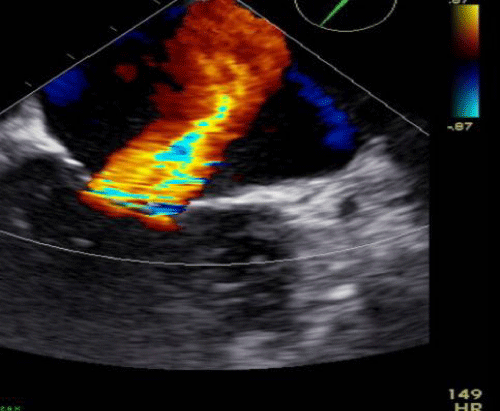

Cine 3: AF with VR approximately 100-105 bpm. TTE short-axis view at the level of the aortic valve demonstrating severe tricuspid regurgitation (TR) with color flow